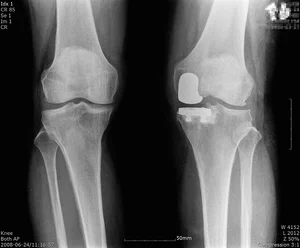

'인공관절' 부담스럽다면 '부분치환' 권장

무릎 퇴행성관절염은 무릎 관절이 노화하고 퇴화하며 염증이 생긴 상태다. 이에 앉을 때, 계단을 오르내릴 때 등 일상생활에서 통증으로 많은 어려움을 초래하게 된다. 퇴행성관절염 초기에는 약물 등 보존적 치료로 호전을 기대할 수 있지만 차도가 없다면 인공관절 수술을...